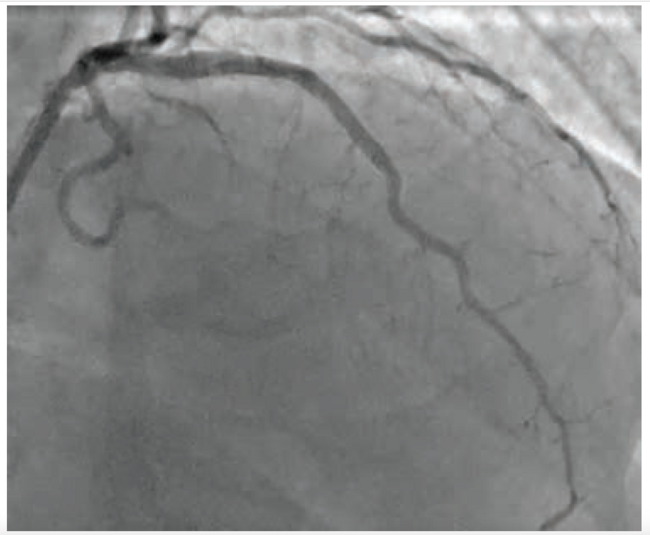

A 4.0 mm IVL was performed without difficulties. Repeat OCT showed significant expansion and both multiplane and longitudinal fractures (Figure 4A-B). A 4.5 mm Onyx stent (Medtronic) was placed and the final angiographic result showed a significant increase in MLA (Figure 5).

This case showcases the need for an adjunctive calcium modification strategy post atherectomy due to the mechanistic limitations of atherectomy within large vessels. Intravascular imaging was critical to help understand the presence, morphology, and treatment strategy of the unmodified calcium present within the vessel. The concentric, deep calcium remaining in the vessel was effectively modified by Shockwave coronary IVL without any procedural complications. The procedural flow and outcome of this case matches the results and conclusions of the Dual-Prep registry — a first-of-its-kind, rigorous, 100% imaging-guided prospective study on the safety and efficacy of IVL post atherectomy within 120 severely calcified coronary lesions.2 As in this case, Dual-Prep investigators chose IVL post atherectomy based on the unlikelihood of efficacy of additional atherectomy within large vessels and were able to achieve desired calcium modification without any notable increase in procedural complications. This real-world case also supports the Dual-Prep conclusion that it may be possible to facilitate better stent expansion and eccentricity with a rotational atherectomy and IVL combination strategy versus a standalone atherectomy or alternative combination strategy.